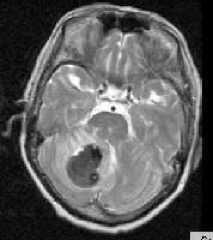

МРТ головного мозга. Аксиальная Т2-взвешенная МРТ. Кровоизлияние в мозжечок.

Интрапаренхимальные кровоизлияния являются следствием гипертонии и проявляются в виде кровоизлияний в вещество мозга (геморрагический инсульт) и гипертензивных синдромах. Геморрагический инсульт возникает вследствие разрыва изменённых (гиалиноз, микроаневризмы) сосудов при повышении артериального давления. Частота геморрагического инсульта составляет около 9 случаев на 100 тысяч населения. Это 10-18% от всех смертей. По отношению к всем острым нарушениям мозгового кровообращения (ОНМК) на геморрагический инсульт приходится 10-20%. Кроме того, еще наблюдаются вторичные диапидезные кровоизлияния при ишемическом типе ОНМК. Также кровоизлияния типичны для венозных инфарктов. Возраст пациентов обычно старше 45 лет. Локализация геморрагического инсульта может быть почти любой, но чаще это базальные ядра, таламус, мозжечок.